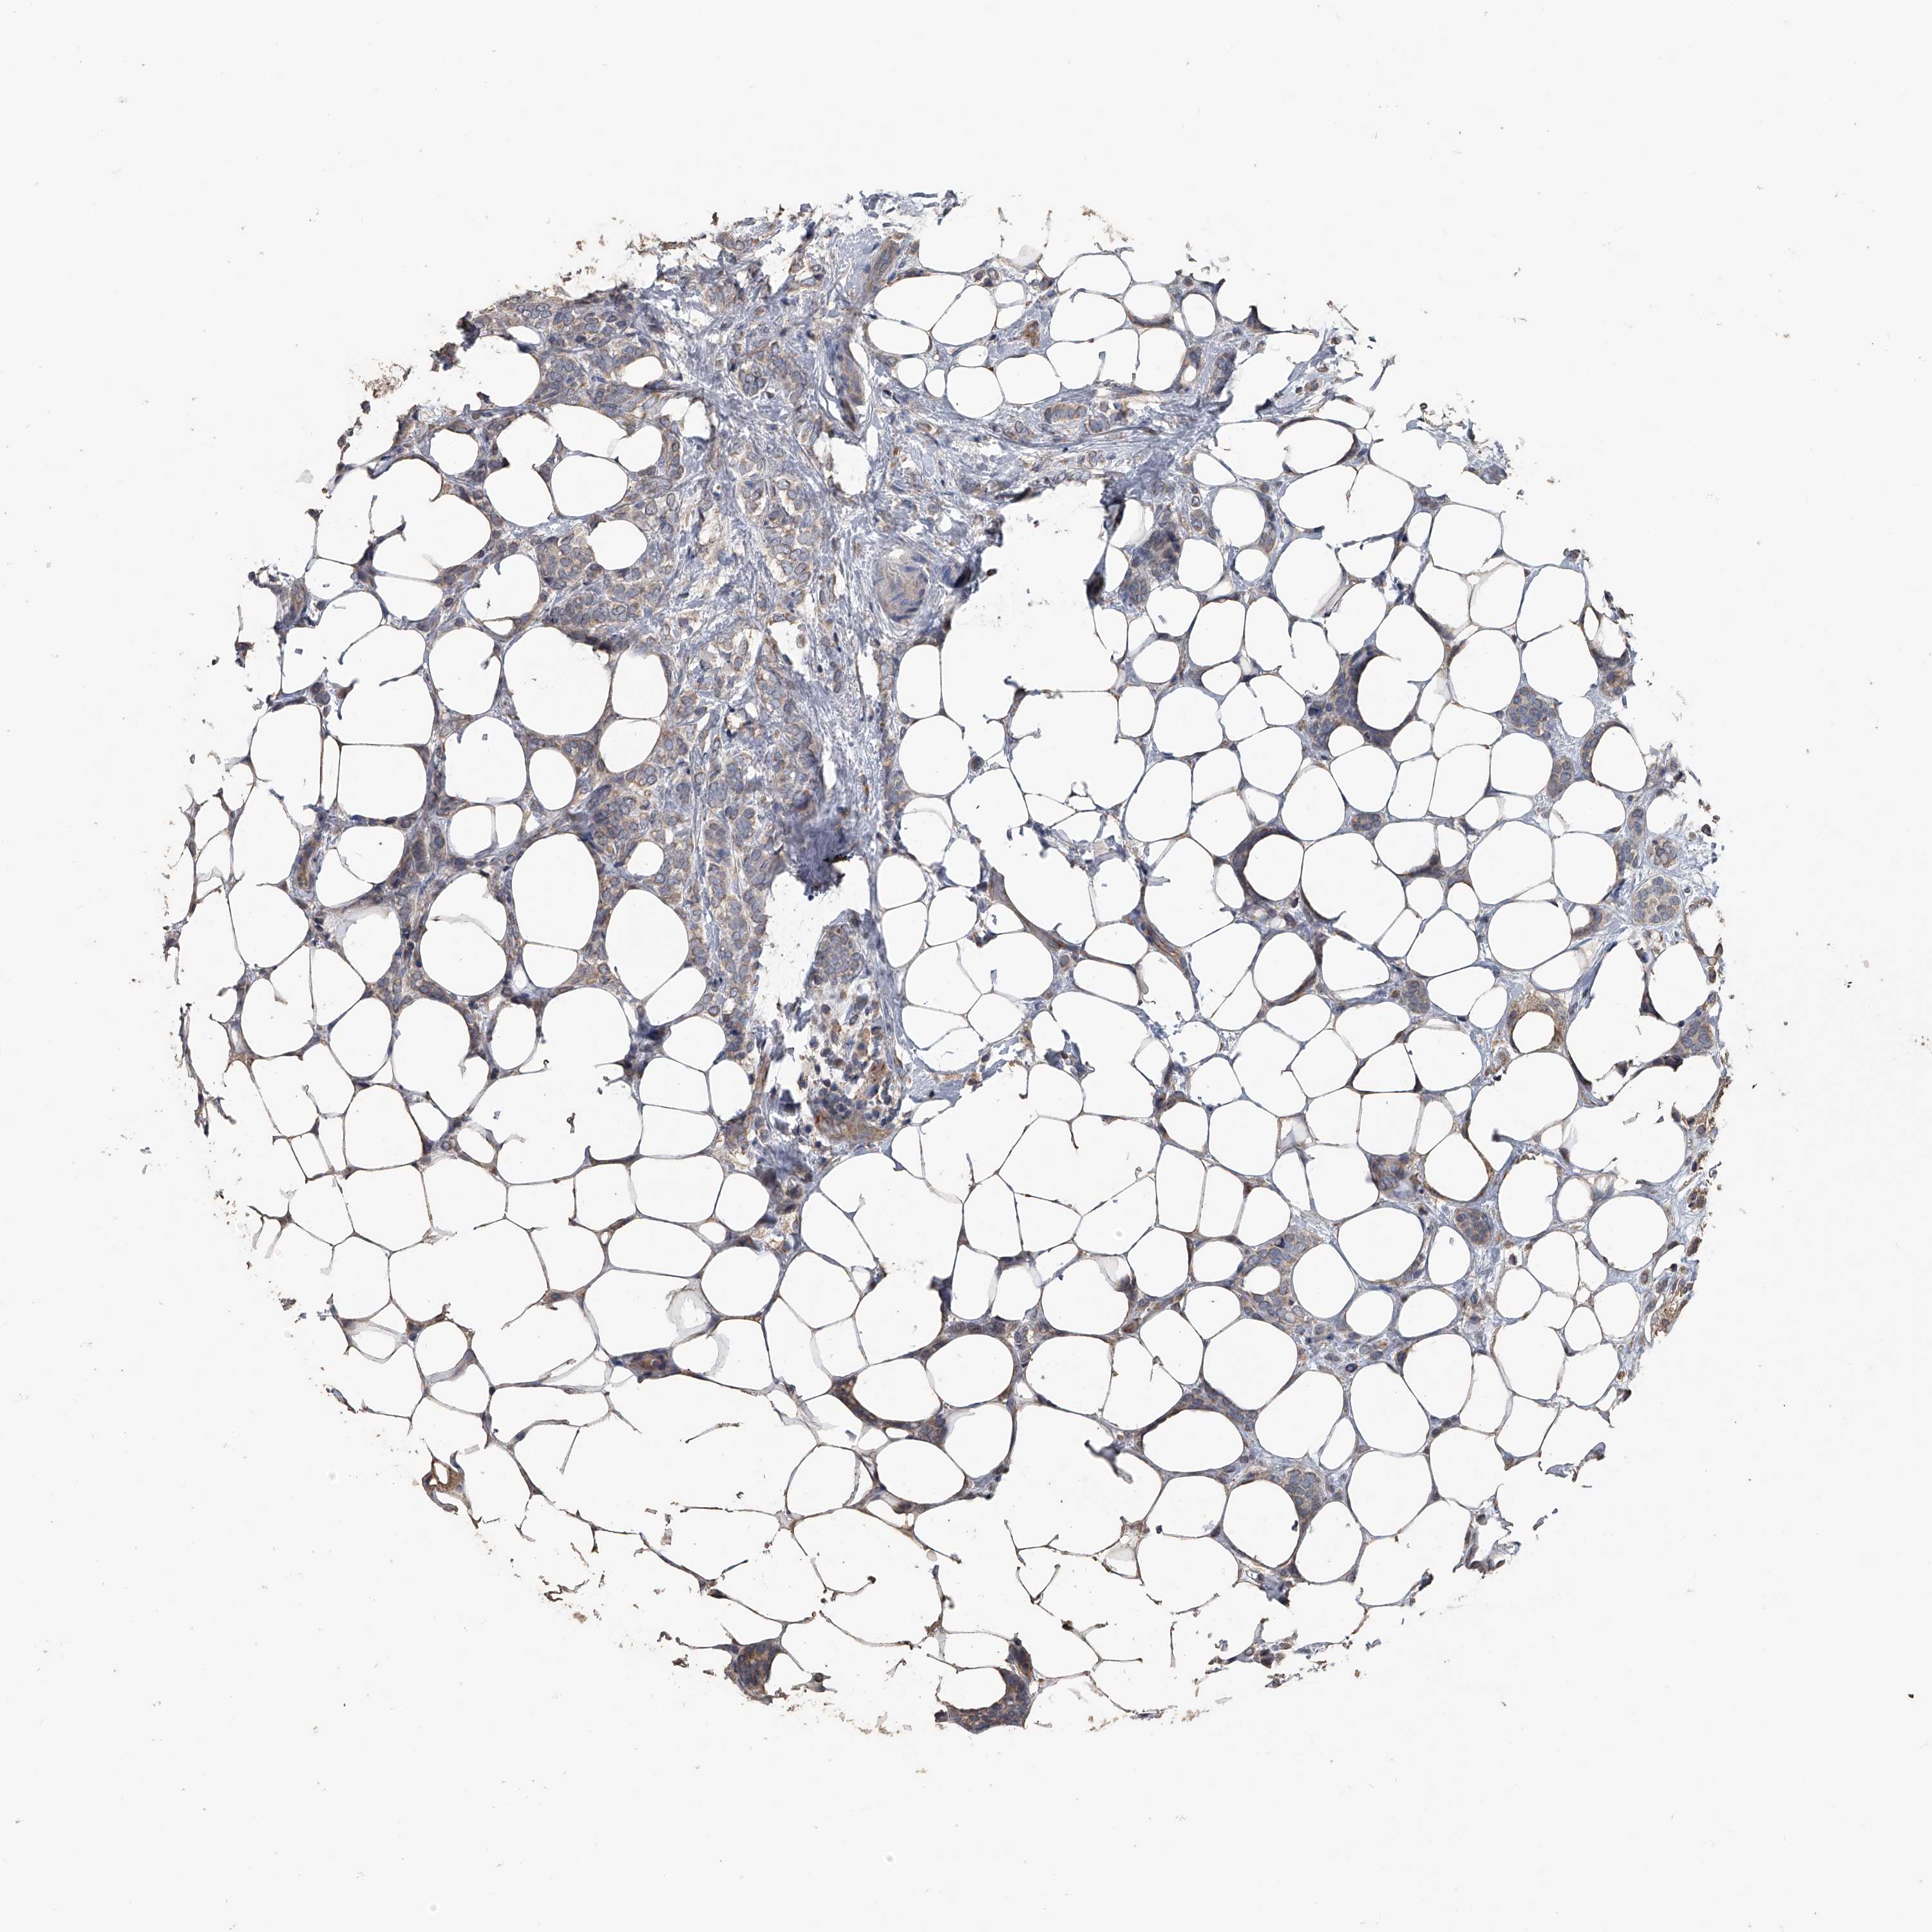

CANCER BREAST CANCER Show tissue menu

BRCA TCGA BRCA VALIDATION PROTEIN EXPRESSION

ANTIBODIES

AND

VALIDATION